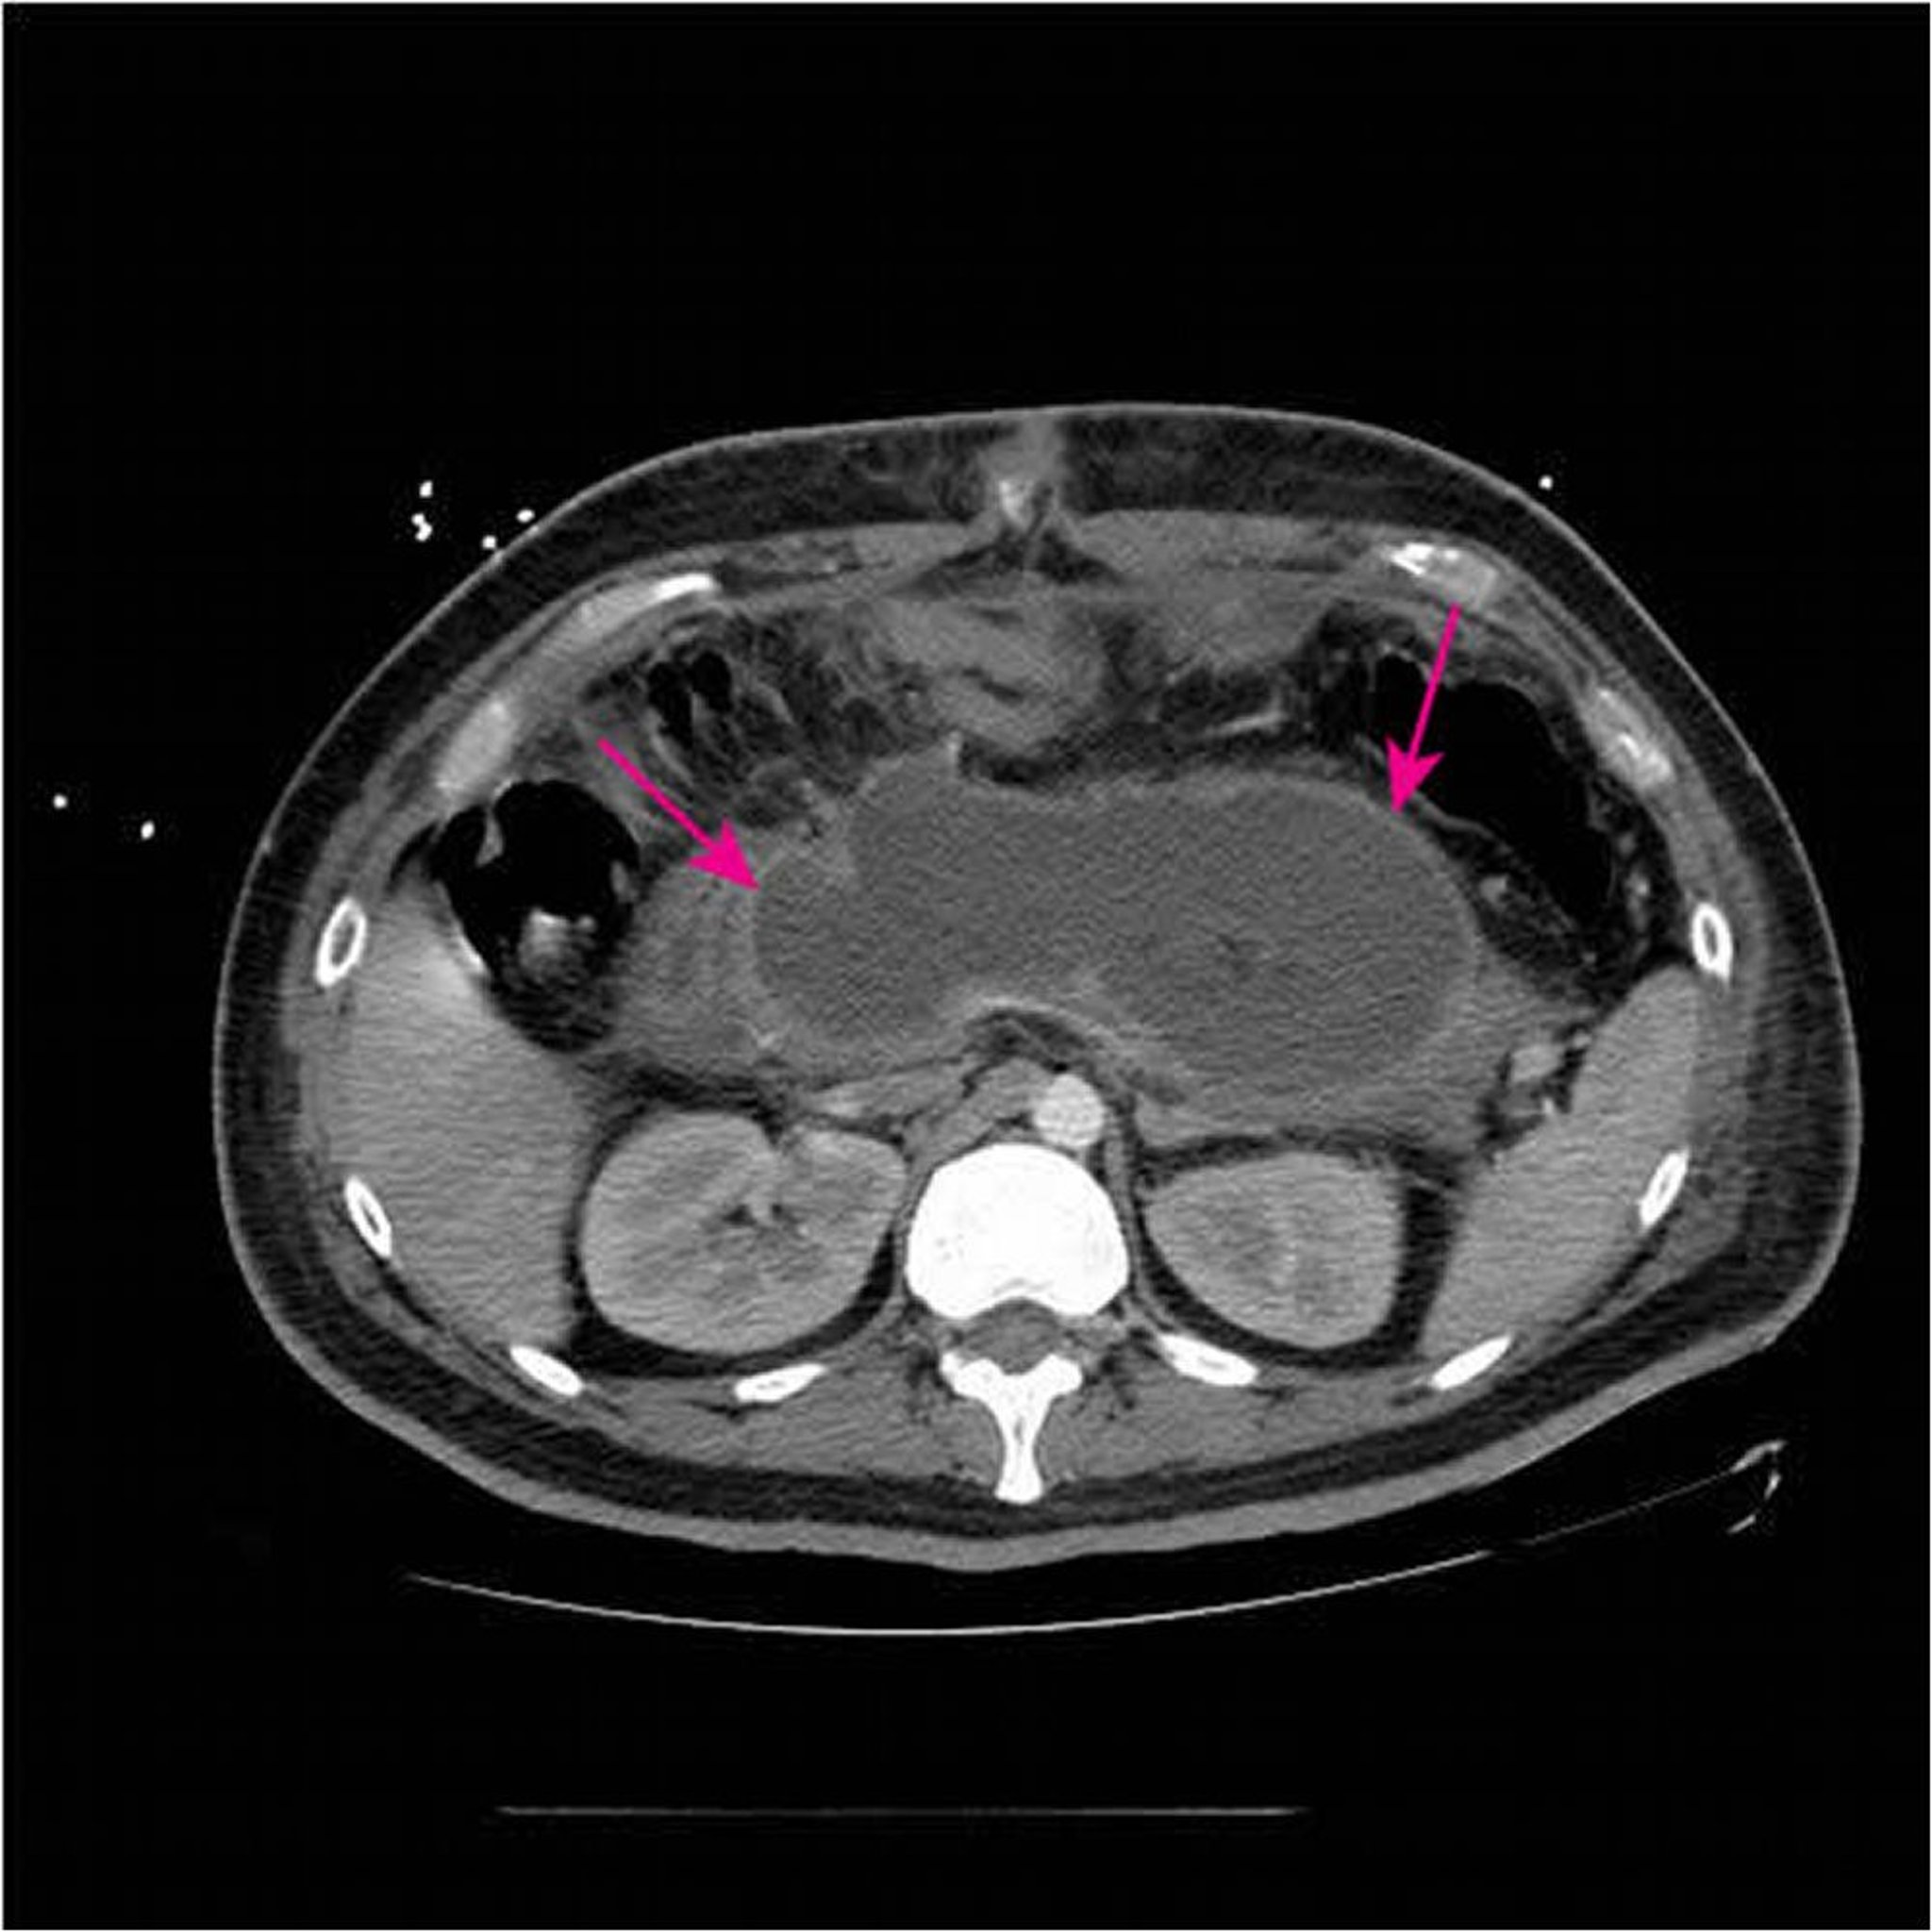

Essa TC com contraste IV e oral mostra grande coleção necrosante aguda (setas) substituindo a maior parte do tecido pancreático < 4 semanas desde a apresentação inicial de pancreatite necrosante.

Imagem cedida por cortesia de Sonam Rosberger, MD.